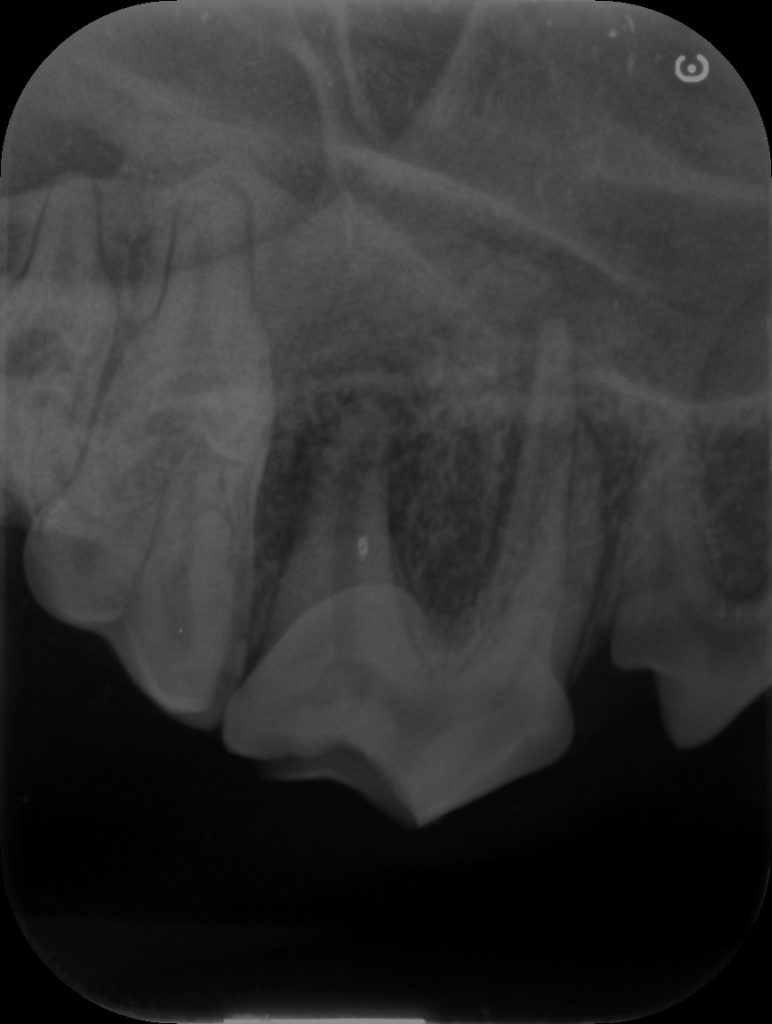

この子もレントゲンを撮影すると

わかりにくいと思いますが、このような範囲で骨が溶けている変化が見られます。

このまま放置をすると顔が腫れたり、膿が出た可能性があります。